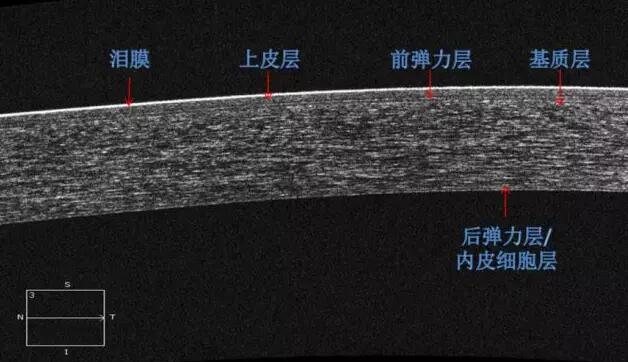

角膜篇

1、角膜分层观察 OCT 轴向分辨率高达5μm,远高于UBM(20--60μm),可识别出泪膜、上皮层、前弹力层、基质层、后弹力层/内皮层